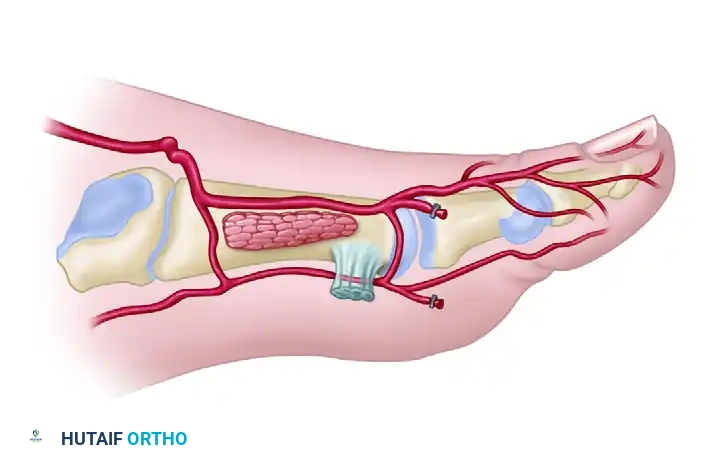

Venous Drainage and Innervation

- Venous: The flap is drained by two systems: the deep venae comitantes accompanying the DPA, and the superficial venous system draining into the greater saphenous vein. Both should be harvested to ensure robust venous outflow.

- Innervation: The superficial peroneal nerve provides sensory innervation to the dorsal skin. Its branches can be identified proximally and included in the flap for sensate reconstruction.

4. Vascular Dissection and Pedicle Isolation

- Retract the EHL tendon medially to expose the periosteum overlying the first metatarsal.

- Identify the dorsalis pedis artery (DPA), its accompanying venae comitantes, and the deep peroneal nerve.

- Continue the dissection laterally and distally to trace the DPA. Identify the origins of the first dorsal metatarsal artery (FDMA), the arcuate artery, and the deep plantar (communicating) artery.

- Once the deep plantar artery is definitively identified plunging plantarly, carefully ligate and transect it. This mobilizes the distal DPA and FDMA.